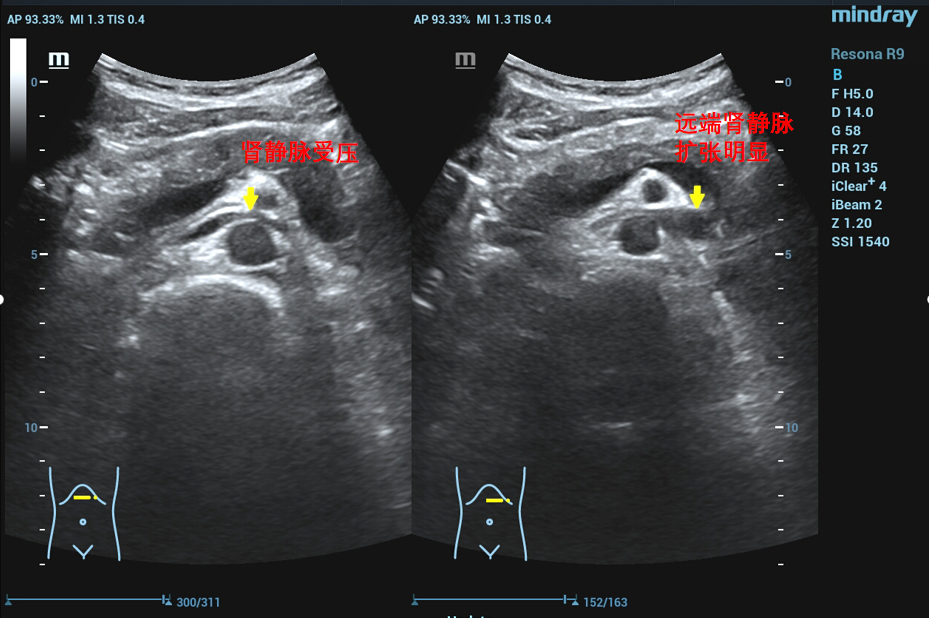

患者于两年前无明显诱因出现肉眼血尿及排尿疼痛,偶有左侧腰部疼痛,无明显精索静脉曲张,曾于基层医院就诊行CT等检查提示左肾静脉压迫综合征,也就是胡桃夹综合征。为进一步的诊治前来亚洲色吧 附二院就诊,经过泌尿外科三病区详细的检查和判断,该患者左肾静脉胡桃夹现象比较明显,临床症状比较重。泌尿外科三病区对患者的病情进行反复的讨论,并与患者的家属和患者本人充分沟通后决定行手术治疗。

在泌尿外科三病区柯昌兴主任、杨博伟副主任医师、李宇航博士团队的精心准备和密切配合下,顺利为患者完成“腹腔镜(3D)下左肾静脉外支架置入术”。术中,见左肾有3根动脉,其中一根动脉绕行并压迫左肾静脉(术前阅片已确认),左肾静脉入肠系膜上动脉与腹主动脉夹角处,其周围纤维条索较多,此处左肾静脉明显变窄,离断纤维条索后此处左肾静脉明显增宽,充分游离左肾静脉近端至下腔静脉,远端至“其中一根动脉绕行并压迫左肾静脉”处,离断左性腺静脉和肾上腺中央静脉。柯昌兴主任团队成功放置一根6cm长带外支撑环的人工血管固定在患者左肾静脉外面,为受压的左肾静脉支撑起一条“生命通道”,提供持久的支撑力对抗肠系膜上动脉和腹主动脉的压迫。整个手术非常顺利,耗时约3小时,出血约10毫升。术后3天,患者康复出院,且腰痛、血尿等术前临床症状明显缓解,手术效果非常显著。

胡桃夹综合征,也称胡桃夹现象。是指左肾静脉回注下腔静脉过程中,需穿经由腹主动脉和肠系膜上动脉形成的夹角内受到挤压而引起的血尿、蛋白尿和左腰腹疼痛等临床症状。又称为左肾静脉受压综合征。近年来随着诊疗技术的发展。胡桃夹综合征引起的血尿发病率呈逐渐上升趋势,越来越受到临床的关注。

正常情况下,腹主动脉与肠系膜上动脉所形成的夹角为45度到60度,并为脂肪、淋巴、纤维结缔组织等填充,而左肾静脉并不受压。因为某些情况下可使夹角变窄,左肾静脉受压,导致左肾瘀血、肿大,以及左生殖腺静脉瘀血、曲张。